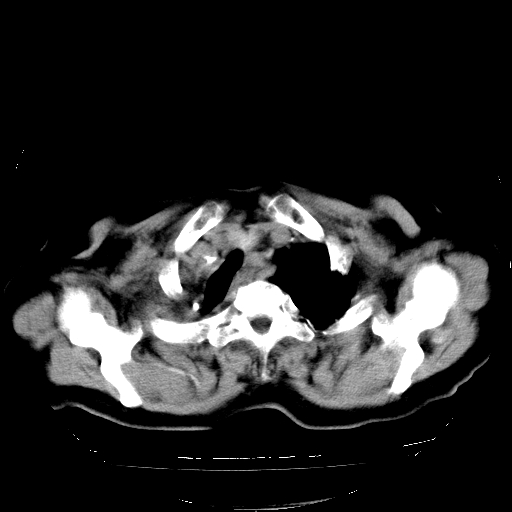

标题: CT23991:女,72岁,咳嗽、憋气一周。 [打印本页]

女,72岁,咳嗽、憋气一周,十年前曾患肺结核及胸膜结核。

右侧毁损肺,右侧纵隔疝

右侧毁损肺,右侧纵隔疝,左肺代偿!

1.右侧损毁肺伴胸膜钙化,2.左肺小结节灶,良性可能大,注意复查。3.肝脏左叶囊肿。4.先天性一侧肺不发育待出外(右侧胸廓无明显塌陷)。对比原片应该非常有帮助。